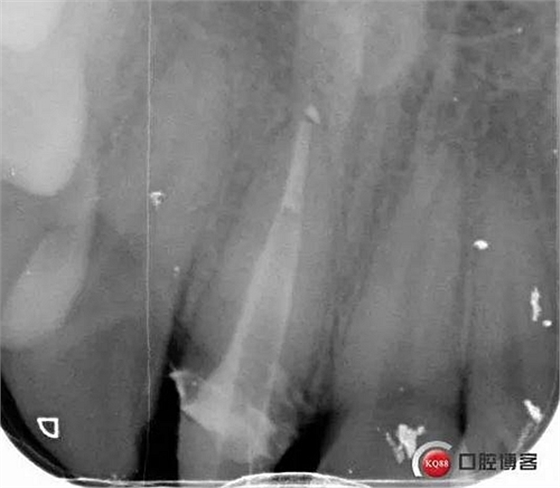

術(shù)后牙片可以看出樁的長(zhǎng)度有明顯增加。到達(dá)預(yù)備長(zhǎng)度。術(shù)后齦緣高度與鄰牙一致